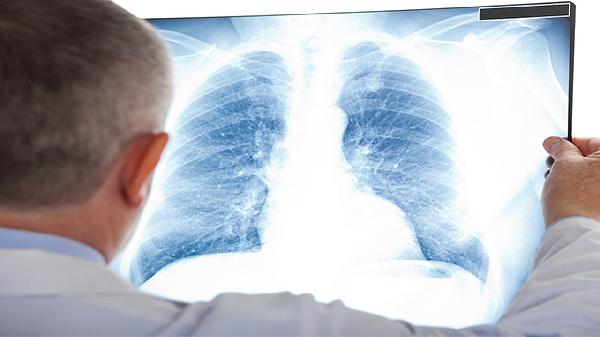

脑炎诊断通常需要脑脊液检查、脑电图或头颅磁共振成像等检查。肺炎诊断主要依靠胸部X线或CT检查,结合痰培养或血常规等实验室检查。两者的诊断路径和检查重点有明显区别,需要针对性选择检查手段。